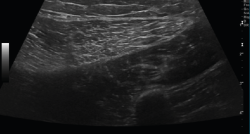

El ultrasonido se puede usar en el diagnóstico de numerosas patologías y puede guiar en procedimientos diagnósticos y terapéuticos(5).

Su indicación fundamental es en el diagnóstico de las lesiones de partes blandas superficiales.

Las estructuras específicas más adecuadas para este estudio incluyen tendones, músculos y ligamentos, además de masas periarticulares de tejidos blandos. Es útil para el diagnóstico de derrame articular, engrosamiento sinovial, bursitis, cuerpos libres intraarticulares, gangliones, quistes, roturas ligamentosas y tendinosas, tendinitis y fracturas ocultas(6).

En el estudio musculoesquelético se utiliza una sonda lineal con alta frecuencia, de entre 9 y 13 mHz.